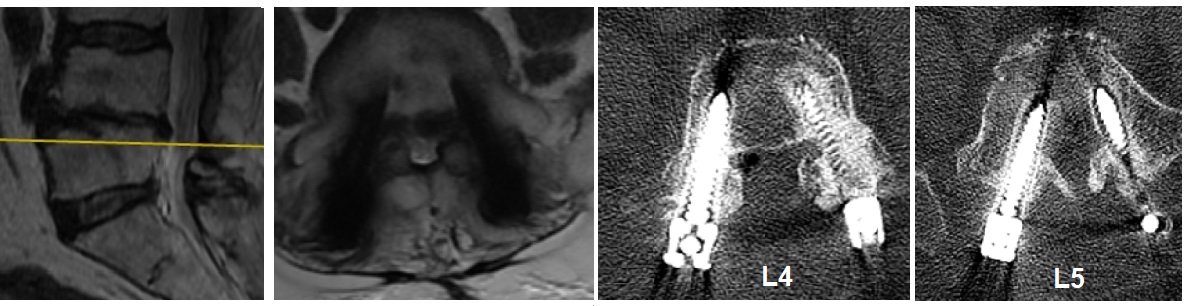

2022 Yılı MRG İncelemesi ve Myelografi

Resim 2: Yaptırılan MRG incelemesinde median, sağ ve sol paramedian kesitler ve MR-myelografi incelemesi görülmekte. Alt seviyelerde santral stenoz yoktur, T10-T11 seviyesi ise şüphelidir. Ancak paramedian kesitlerde T9-T10, T10-T11, L4-5 ve L5-S1 seviyelerinde lateral reses ve foramen stenozları şüphesi vardır. İmplantların artefaktı ideal bir değerlendirmeyi engellemektedir.

2022 Yılı BT İncelemesi - Vida Gevşemesi

Resim 3: BT incelemesinde T10-T11 ve L4-L5 diskleri içinde ve ayrıca kanal içinde L4 korpusu arkasında gaz ile uyumlu hipodansite, L4 ve L5 vidalarında iki yanlı gevşeme ve foraminal stenozlar görülüyor. Ayrıca L3-4 ve L4-5 seviyelerinde faset füzyonlarının tam oluşmadığı görülmekte. Diğer vidalarda gevşeme ya da malpozisyon yoktur.